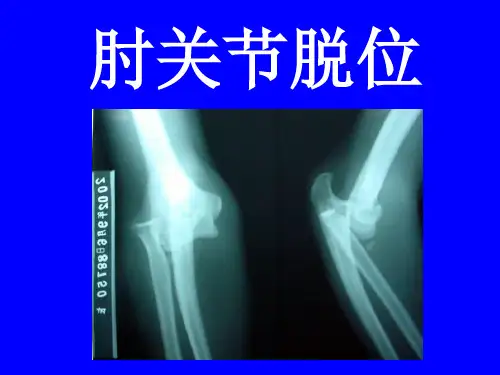

影像学检查是确诊肘关节后脱位的重要手段之一。

常用的影像学检查方法包括X线和CT扫描。

X线能够直观地显示肘关节的骨折、脱位情况以及其他异常情况,如软组织肿胀、关节结构损伤等。

CT扫描可以提供更为详细准确的肘关节三维结构,有助于确定脱位的具体类型和范围。

诊断:根据导致肘关节脱位发生机制及X线正侧位片即可诊断,应仔细观察肘关节X线正侧位片,排除肱骨远端骨折、桡骨头骨折、冠突骨折。